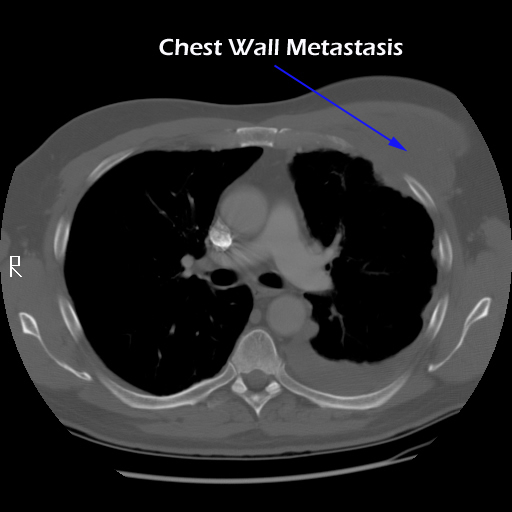

Eleven months later, he presented with a several month history of a painful fixed, firm mass over the pectoral area of the left chest and a smaller mass inferior to this (Figure 1). CT scan demonstrated a new 2 cm nodule in the left upper lobe associated with an anterior chest wall mass six centimeters in size in addition to bilateral new pulmonary nodules (Figure 2). The mass was tethered to the skin and in danger of eroding through it. The patient underwent en-bloc resection of the chest wall and adjacent lung (Figures 3a-c). The resulting defect (Figure 4a) was reconstructed with 2 mm Gore-Tex patch (Figure 4b) and pectoralis major muscle flap (Figure 4c) with primary skin closure (Figure 4d). The pathology revealed metastatic chordoma (Figures 5a-d). The patient recovered well, leaving the hospital on the sixth postoperative day.

Most chordomas are slow-growing lesions, with a tendency to recur locally. This case demonstrates that extensive metastases to the lungs and chest wall may occur. The treatment for the primary tumor is surgical excision with postoperative radiation therapy. However, there is a high incidence of recurrence (25-64%) due to an inability to achieve either an adequate surgical or radiation margin. These tumors can be life-threatening by direct extension or metastasizing to other organs, including the lungs (20-30%) and posterior mediastinum [4, 5]. The five year survival rate for metastatic disease is approximately 50%. Chordomas may also involve the skin (chordoma cutis) by direct extension or distant metastases [3, 6]. However, metastases to the chest wall are extremely rare, there being only one other reported case in the literature [6].

The appropriate treatment for chest wall metastases for chordoma is not known due to the rarity of this occurrence. Indications for chest wall metastasectomy include resection for diagnosis, local control, and palliation / prevention of skin ulceration and rarely for cure or as part of a multidisciplinary approach [7]. While radiation therapy is another option for local control, its ability to prevent progression of disease is unpredictable and unknown in the case of chordoma. Once the area of the chest wall has been irradiated, subsequent resection and reconstruction is more difficult and prone to failure [8, 9]. In the presented case, resection was performed for local control, pain relief and to prevent the complications of ulceration, necrotizing infection and bleeding from a tumor eroding through the anterior chest wall. The principles of chest wall resection were adhered to by performing a full thickness en-bloc resection of the mass, reconstruction with a two mm Gore-Tex patch and coverage with a well-vascularized myocutaneous flap.